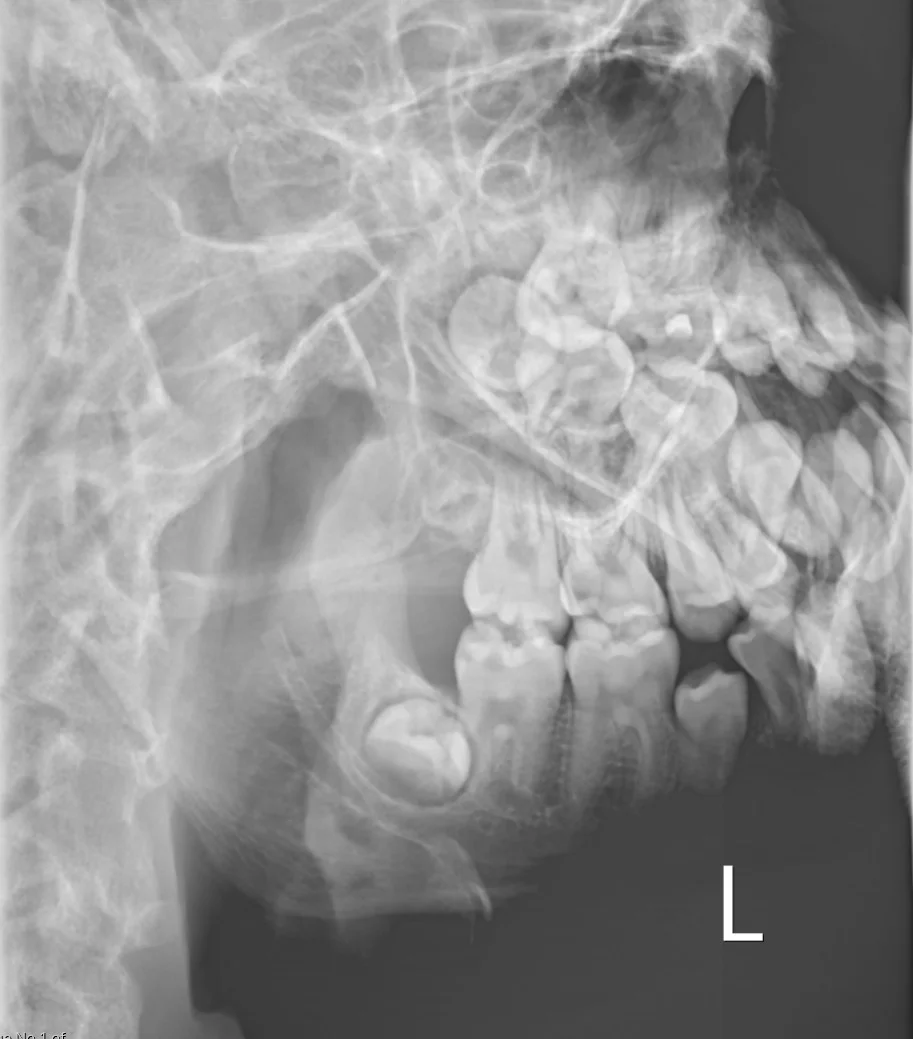

Experience authentic FRCR 2B preparation with our professional DICOM viewer displaying full lossless images at diagnostic workstation quality. Access 1,250+ short cases and 600+ long cases – all created by expert radiologists with zero AI-generated content.

MyFRCR is the UK's premier FRCR 2B exam platform, offering 1,250+ authentic short cases with 2,000+ radiographs and 600+ long cases with 1,000+ cross-sectional images. Our commitment to non-AI, expert-created content with full lossless DICOM quality ensures candidates receive genuine exam preparation.

2,000+ radiographs and 1,000+ cross-sectional images in full lossless DICOM format.

Zero AI content – all cases created by expert consultant radiologists.